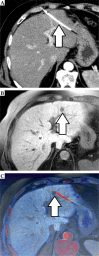

Material and methods: We report a retrospective analysis of 100 patients treated on 233 HCC lesions by HDR-BT (using 588 catheters in total). No needle or catheter track irradiation was used. Minimum required follow-up with imaging was 6 months. In case of suspected needle track seeding (intra- and/or extrahepatic) in follow-up, image fusion of follow-up CT/MRI with 3D irradiation plan was used to verify the location of a new tumor deposit within the path of a brachytherapy catheter at the time of treatment.

Results: We identified 9 needle track metastases, corresponding to a catheter-based risk of 1.5% for any location of occurrence. A total of 7 metastases were located within the liver (catheter-based risk, 1.2%), and 2 metastases were located extrahepatic (catheter-based risk, 0.3%). Eight out of 9 needle track metastases were successfully treated by further HDR-BT.